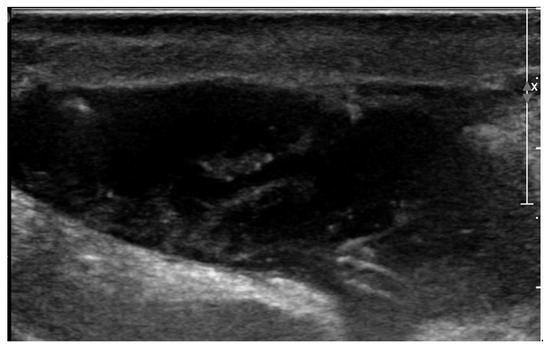

After discharge, the postoperative period went uneventful, but on the fifth postoperative day the owner noticed lethargy, anorexia, and severe exercise intolerance, when the dog could hardly walk more than 25 m. The dog was presented to the emergency service of the authors’ institution at night. Physical examination revealed a lethargic dog with a respiratory rate of 30/min, a pulse rate of 60/min and a rectal temperature of 39.5 °C. Both wounds, on the right chest and over the right jugular vein region appeared normal, without redness, discharge or pain. However, a seroma formation was suspected around the cervical wound because this region was mildly swollen. With a blood test, a moderate leukocytosis was found (24.0 × 109/liter, reference 4.5–14.6 × 109/liter) due to neutrophilia (21.8 × 109/liter, reference 2.9–11.0 × 109/liter). Plasma creatinine (139 µmol/l, reference range 50–129 µmol/l) and lactate (2.89 mmol/l; reference 2.0–2.5 mmol/l) concentrations showed mild elevation and the plasma albumin concentration (21 g/l; references 26–37 g/l) was slightly decreased. Hematocrit and plasma biochemistry panel showed that blood urea nitrogen, total protein, potassium, sodium, chloride, calcium, glucose concentrations, and the pH were within the reference range. The dog was hospitalized. The next morning the cervical wound looked not only more swollen, but also it became red, warm, and painful. A bacterial infection of the subcutaneous part of the pacing lead was suspected and an ultrasonographic examination of the swollen cervical region was performed. Ultrasonography showed that the subcutaneous portion of the pacemaker lead was surrounded by a mild amount of anechoic fluid. At the region where the lead entered the right external jugular vein, a larger pocket of fluid (3.4 cm × 0.9 cm) was found, where the fluid was mainly anechoic with some echogenic threads (Figure 4). The subcutaneous fat around the fluid accumulation appeared diffusely hyperechoic.

Figure 4. Two-dimensional grayscale ultrasonographic image of the swelling at the level of the surgical wound of the jugular venous incision shows a pocket of fluid accumulation.